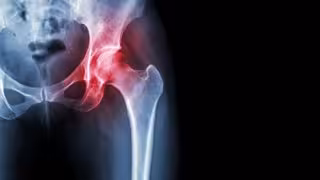

Necrosis avascular de cadera - HOSPITAL LA LUZ

Esta enfermedad, conocida también como necrosis avascular, consiste en la falta de vascularización y aporte sanguíneo al hueso en la cabeza del fémur. "Puede curar espontáneamente o llevar a una deformidad del hueso y de la articulación, llegando a producir dolor intenso e incapacidad para caminar. Así en muchas ocasiones requiere implantar una prótesis total de cadera. La ONCF es una enfermedad de causa desconocida en la mayoría de los casos, pero está muy relacionada con algunos factores como la ingesta de alcohol o tratamientos con corticoides", ha dicho.